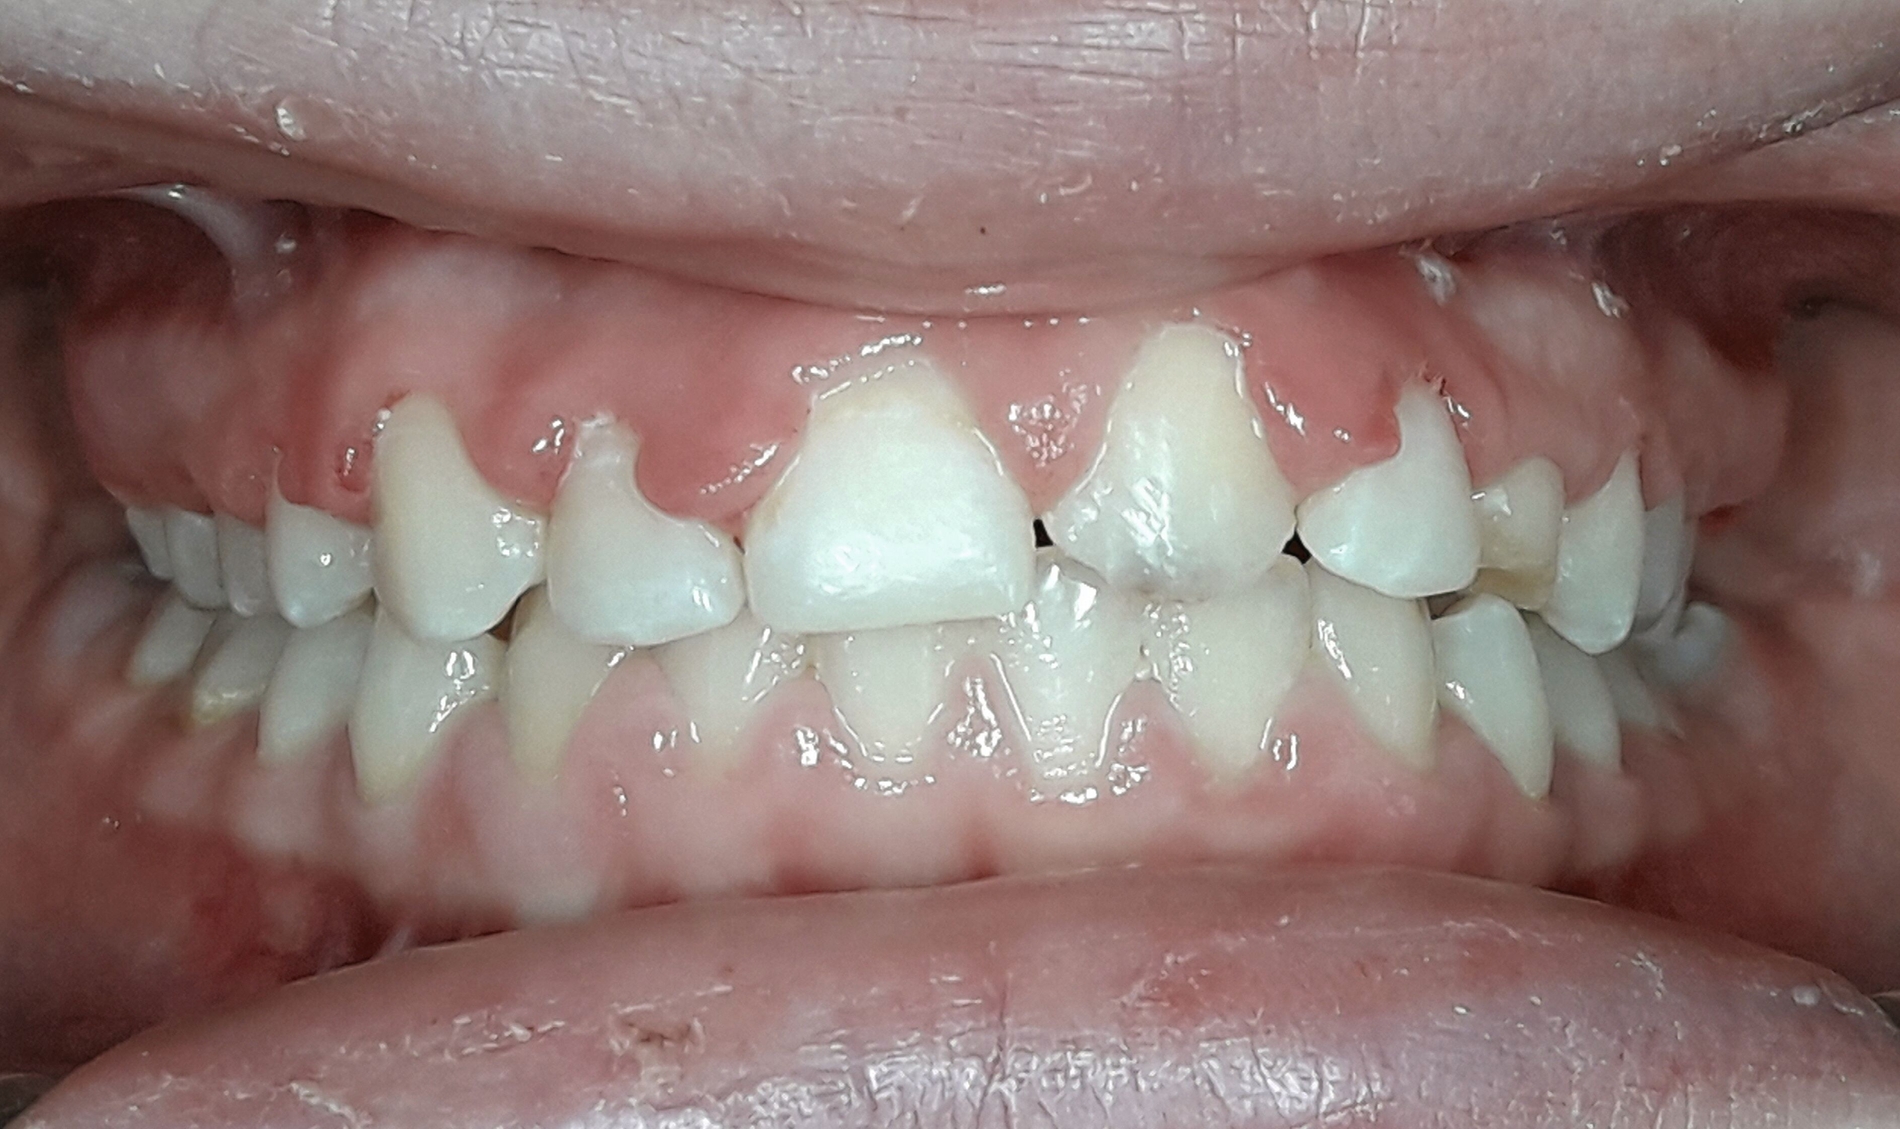

Die kieferorthopädische Behandlung der Patientin wurde im Mai 2018 (alio loco) begonnen. Zu diesem Zeitpunkt war die Patientin zehn Jahre alt. Bei der Erstellung des Behandlungsplans wurde der Fall initial als fehlender linker Eckzahn im Oberkiefer diagnostiziert. Vor der Extraktion des Schneidezahns wurde eine CT-Aufnahme durch den Erstbehandler angewiesen. Die Bildgebung ergab, dass der obere mittlere Schneidezahn sowie der Eckzahn auf der linken Seite betroffen waren (Abbildung 1). Die Patientin wurde daraufhin vom Erstbehandler zur Extraktion des impaktierten Zahnes 21 überwiesen.